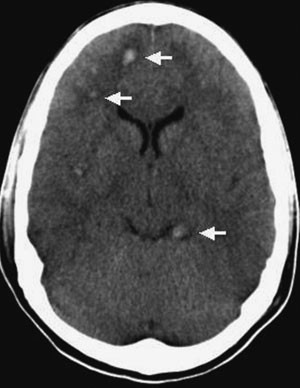

Bildediagnostikk med CT

Ved hodeskader vil CT-undersøkelse av hjernen være førstevalg siden undersøkelsen i akuttfasen er en rask og effektiv teknikk for å påvise frakturer, blødninger og ødem (25). Funn ved cerebral CT hos pasienter med skjærende skade ble først beskrevet i slutten av 1970-årene (9). Pasientene hadde alvorlig klinisk status, men CT viste likevel ikke en signifikant intrakranial blødning som kunne forklare bevisstløsheten. Typiske CT-funn ved diffus aksonal skade er små, punktformede blødninger i overgangen mellom grå og hvit substans i storhjernen og sjeldnere i corpus callosum, blod i ventrikkelsystemet og blod i subaraknoidalrommet rundt mesencephalon (fig 1) (10, 17, 20, 26). Ikke-hemoragiske lesjoner er vanskelige å påvise ved CT (25). CT vil derfor undervurdere forekomst og omfang av den diffuse aksonale skaden. Pasienter med slik skade kan ha normal CT (18). I senfasen vil CT i de mest alvorlige tilfellene kunne vise atrofi med økt ventrikkelstørrelse (9).